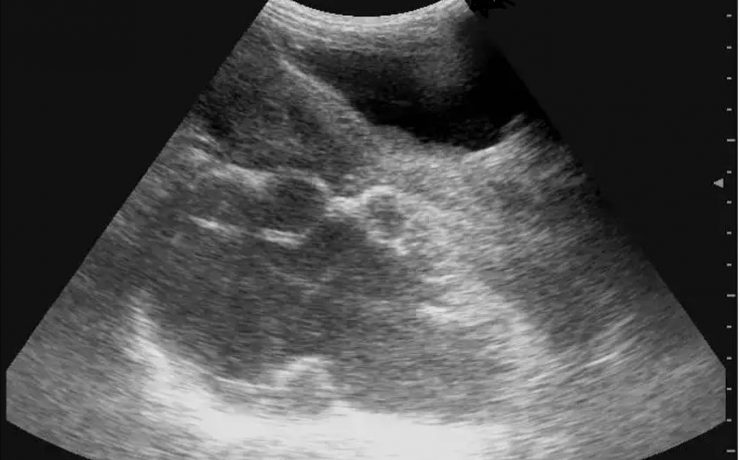

El cólico nefrítico se define como un dolor agudo en el flanco (en ocasiones se irradia a la ingle) escrito por los pacientes como el peor de su vida y que generalmente se acompaña de náuseas, vómitos y hematuria. La litiasis es un agregado policristalino compuesto de cristaloides (95%) y